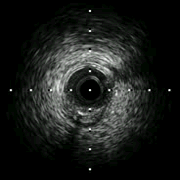

过程(2): 送IVUS导管至前降支近中段,回撤评估左主干-前降支病变情况。左主干末端MLA 2.58mm2,斑块负荷87%。